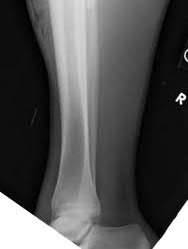

Figure A demonstrates an AP radiograph of a Weber B fibula fracture with minimal medial clear space widening.

Figure B demonstrates a mortise radiograph of a Weber B fibula fracture with a congruent mortise.

Figure C demonstrates a lateral radiograph of a Weber B fibula fracture with a congruent mortise.

Figure D demonstrates a stress radiograph with minimal medial clear space widening.